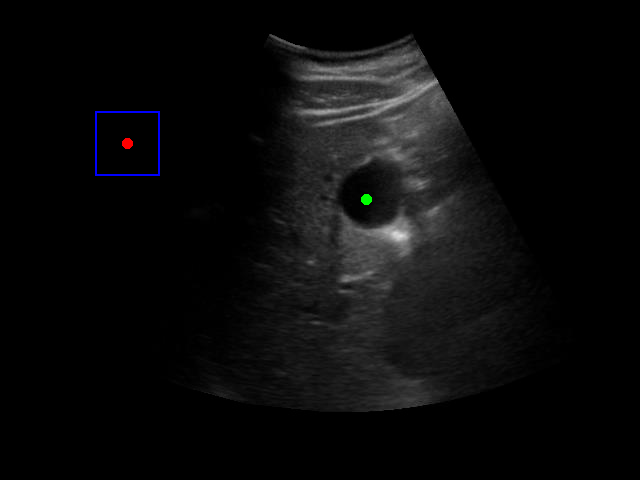

Visualization of the agent's navigation during training (episode 500). The agent learns to navigate efficiently to the target center.

Evaluation Episode

Visualization of the agent's navigation during evaluation. The agent successfully navigates to the target center with minimal oscillations.